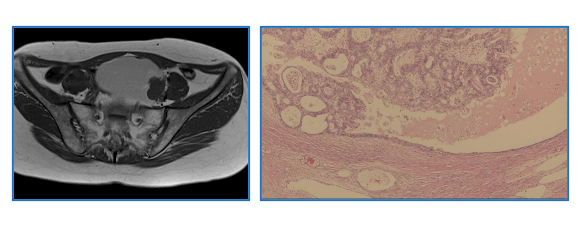

Reproductive endocrinology

Reproductive endocrinology has been the research strength in our department. We extend our research fields to cover obstetrical complications caused by reproductive disorders and endocrine/metabolic disorders such as diabetes mellitus and hypothyroidism.

甲状腺自己抗体を保有する卵巣機能不全患者血清中に見出した新規自己抗体とその抗原タンパクに着

Primary ovarian insufficiency is a big issue as a caused of refractory infertility. We identified the new targets of autoantibody in ovary related with thyroid autoimmunity. We have been developing the assay system for the anti-ovarian antibody and exploring pathophysiology of autoimmune-related ovarian insufficiency.